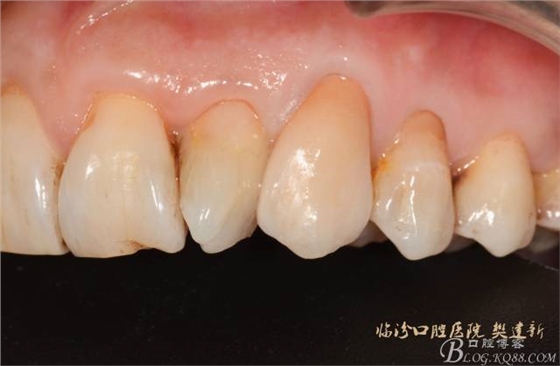

口內(nèi)檢查: 23殘根,位于齦上3MM,根管口探無(wú)反應(yīng),叩(+-),無(wú)松動(dòng),牙周無(wú)紅腫.X片示:23根管無(wú)阻射,根尖骨密度降低.11.12.13頸部楔形缺損,探敏感,牙髓活力正常.全口牙結(jié)石色素(+).

圖123口內(nèi)修復(fù)前情況:殘根位于齦上3MM,牙周無(wú)紅腫.